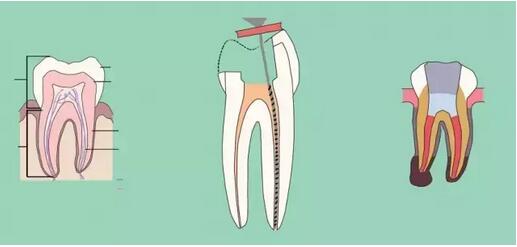

五、根管预备

根管预备的方法无非是采用上面提到的三种(标准法,逐步后退法,冠向深入法)中的哪一种或者或联合法,器械常用而推荐的大致有以下的种类:k挫(10#~40#),c挫(6#,8#,10#),G钻,protaper手用两套不同器械不同的预备方法:

①不锈钢k挫,这套系统常规使用逐步后退法,预备的手法使用平衡力法。

②protaper器械使用逐步深入法,根管系统是很复杂的,任何器械和任何方法的预备都不能到达整个根管系统,所以机械预备和化学预备的结合非常重要(采用尽量小的针头,上下移动轻压冲洗,并防止针头卡住)。

七、根管充填

充填时机,无自觉症状,无明显叩疼,根管内无异味,无渗出,无急性尖周炎症状即可充填,不必等到所有症状消失,反复的封药容易对尖周造成大大刺激。

充填的质控标准:

a、充填物距根尖小于等于2mm;

b、充填致密,连续,锥度合适;

c、充填完毕烫牙胶尖根管口下2~3mm,小号充填器冷加压;

d、对于欠充患者需重新预备充填,而超充原则上不建议重做,随访,必要时根尖手术治疗。目前研究表明,在其他因素相同的前提下,超充的预后差于欠充。